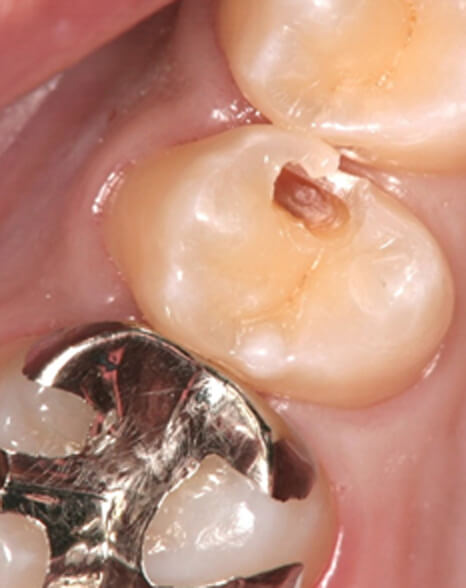

術前

奥歯の詰め物と虫歯が気になるためダイレクトボンディングを希望されました

ダイレクトボンディング 治療後

術後